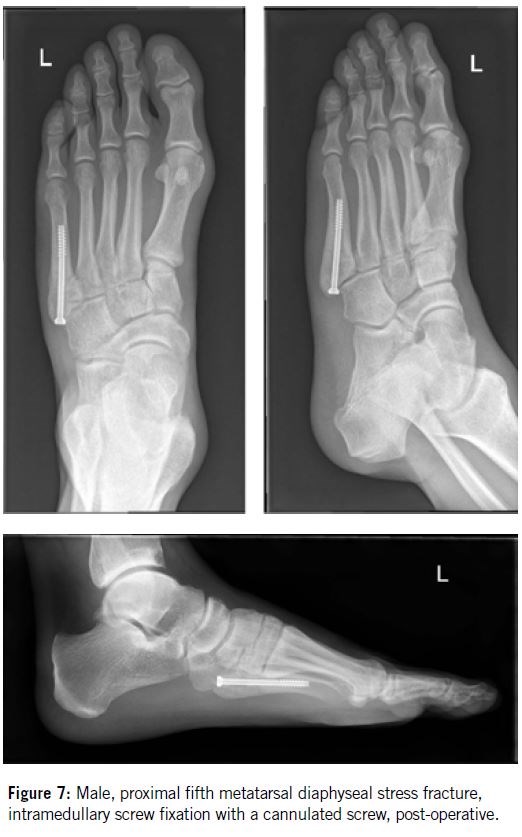

In 1975, Dameron2 was the first to suggest that athletes should undergo early operative treatment to prevent delayed union. Various surgical techniques have since been proposed, including intramedullary screw fixation, plating, percutaneous pinning, intramedullary curettage, and bone grafting (Figures 7 & 8). While the reported union rates with these methods are generally high, several complications have also been documented following their use.

Over the past 25 years, intramedullary screw fixation has emerged as the most widely used surgical technique for treating proximal fifth metatarsal diaphyseal fractures in athletes, with reports indicating improved union rates and faster recovery times. The partially threaded cannulated screw became the gold standard for operative treatment.

More recently, excellent bone healing outcomes have been reported with the use of headless compression screws. It is recommended to use the largest diameter screw that fits the width of the intramedullary canal, with a minimum diameter of 4 mm and a length of at least 50 mm. Proximally, the screw should be positioned to avoid irritation of the cuboid or the fourth/fifth intermetatarsal joint.

Due to the dorsal curvature of the proximal fifth metatarsal, proper care must be taken to ensure that the screw tip aligns as closely as possible with the bone’s axis. However, recent studies have reported several cases of failure following screw fixation in athletes9. The most frequently cited cause of delayed union and refracture is an early return to vigorous physical activity.

In 200512, we published our study detailing the operative treatment of 18 proximal fifth metatarsal stress fractures in 17 professional soccer players. Percutaneous intramedullary fixation using a 4.5 mm malleolar screw was performed in 11 athletes (Group I), while open intramedullary screw fixation combined with autologous cancellous bone grafting was used in the remaining seven (Group II).

Based on our experience, we recommend intramedullary screw fixation combined with autologous cancellous bone grafting as the primary surgical treatment for high-level athletes. To date, we have treated approximately 60 athletes using this technique, including four with bilateral proximal fifth metatarsal fractures. None of these cases resulted in refracture.